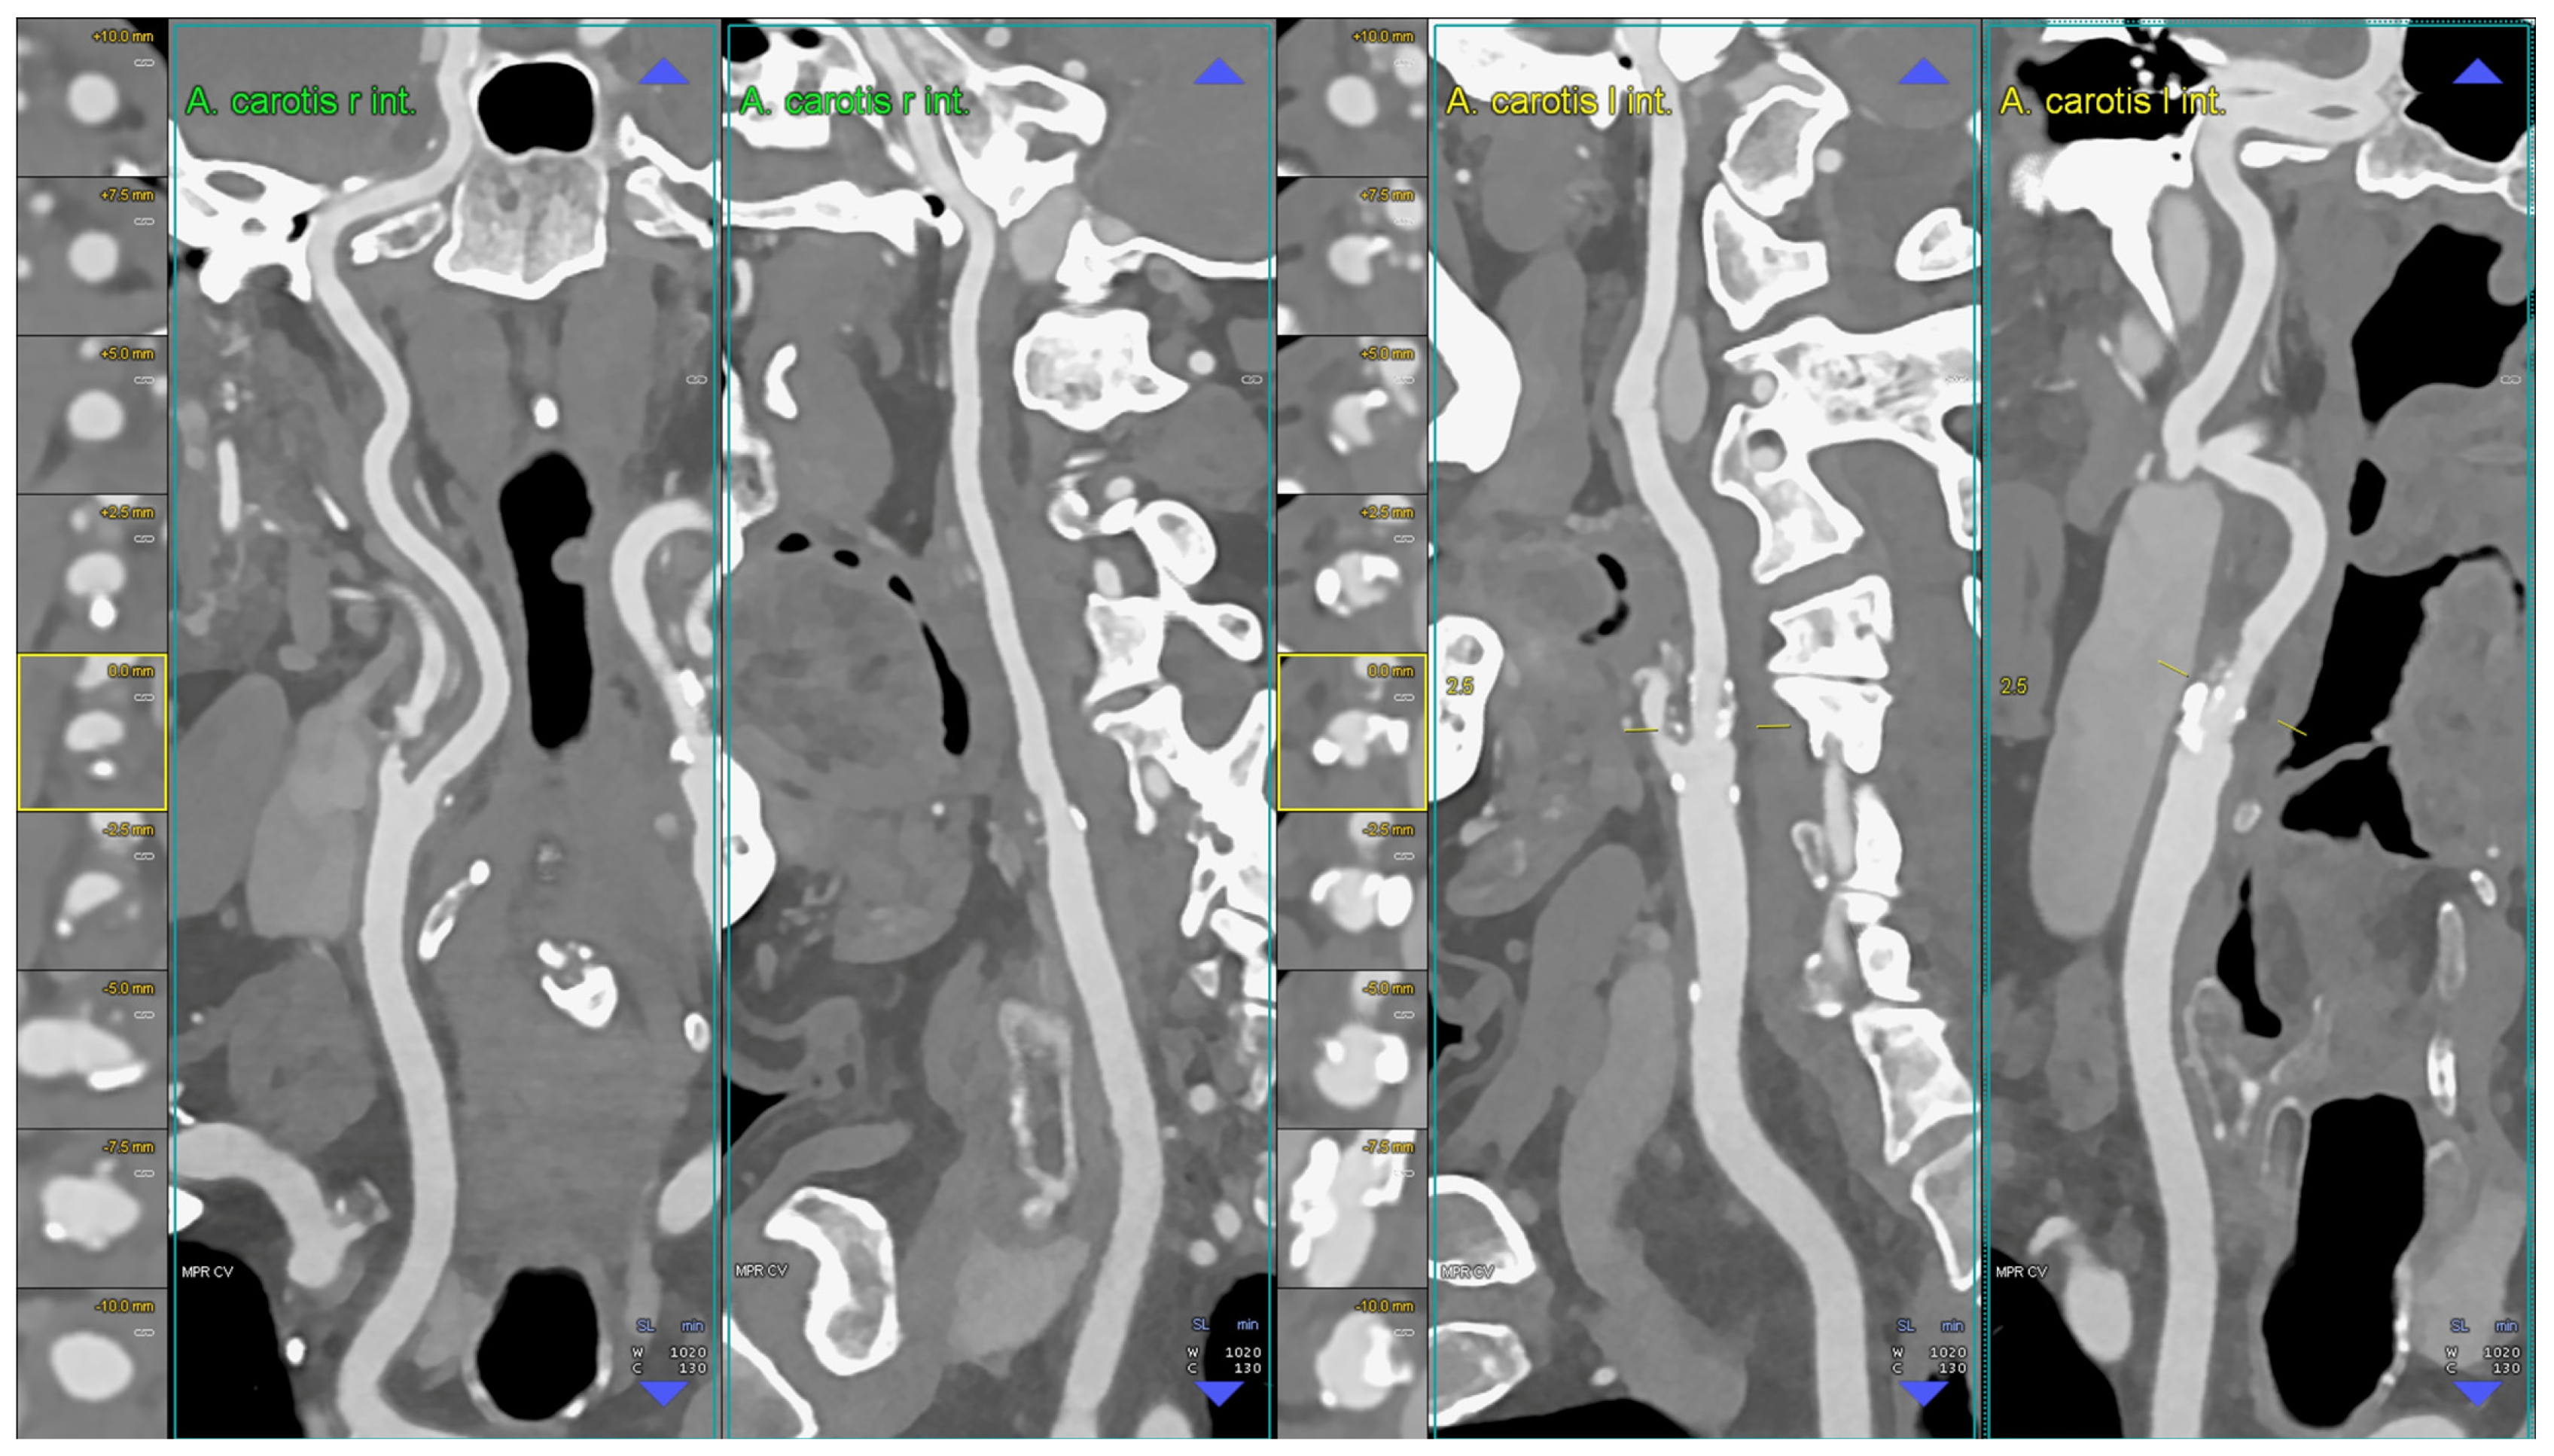

6.1. Carotid Lumen Evaluation

6.2. Carotid Stents